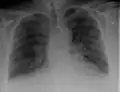

Chest X-rays are frequently used to aid in the diagnosis of CHF. In a person who is compensated, this may show cardiomegaly (visible enlargement of the heart), quantified as the cardiothoracic ratio (proportion of the heart size to the chest). In left ventricular failure, evidence may exist of vascular redistribution (upper lobe blood diversion or cephalization), Kerley lines, cuffing of the areas around the bronchi, and interstitial edema. Ultrasound of the lung may also be able to detect Kerley lines.[72]

Congestive heart failure with small bilateral effusions

Kerley B lines